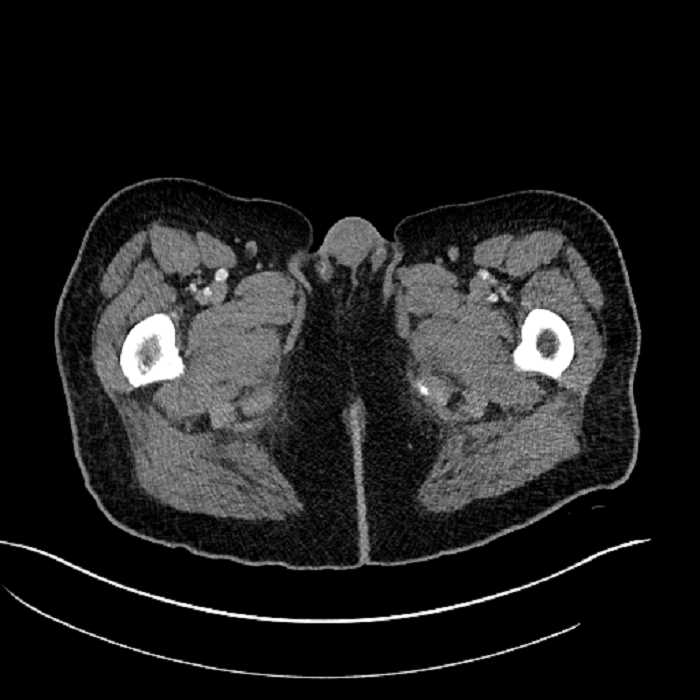

Age: 63

Sex: Male

Indication: Abdominal pain

• High grade stenosis of the left common iliac artery, with the left internal and external iliac arteries remaining patent

• Ankylosis of both sacroiliac joints

Acute sigmoid diverticulitis complicated by a small contained perforation and a large abscess in the right hepatic lobe. Additional small subcapsular abscesses along the anterior margin of the left hepatic lobe.

High grade stenosis of the left common iliac artery. The left external and internal iliac arteries are patent.

Hepatic abscess showing the double target sign with low density internally surrounded by a thin inner enhancing rim (red arrow) and ill-defined outer low density rim (yellow arrow). Blue arrow indicates an internal septation. Red arrows: additional smaller subcapsular abscesses. Red arrow: focal contained perforation associated with diverticulitis.